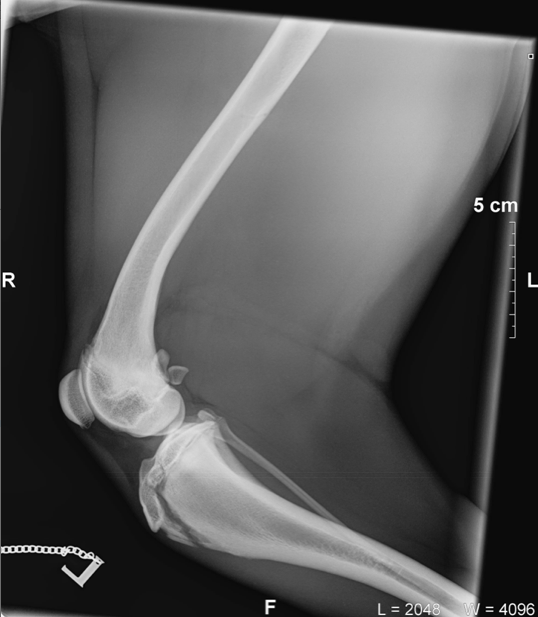

Please look below at all these x-rays from last years random friend’s injuries ( and these are without even searching as these happen all the time). If it is not a growth plate , it is a neck, back, wrist, hock, ribs or any large bones for that matter. One of the most common example is when a small piece of the knee joint splits, which end up in a 2-3000€ surgery. I do not see much point in taking such a huge risk, so don’t run adults and pups! Period!

Here is the proof! More info after the pictures!

Fractures Involving Growth Plates

• Type 3 – elbow (distal humerus)

• Type 4 – elbow (distal humerus)